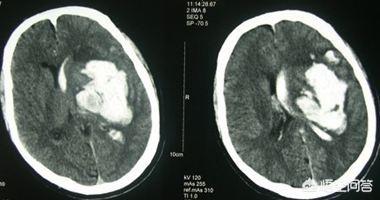

脳出血は、非外傷性因子による脳実質内の出血であり、最も一般的なものは高血圧性脳出血である。

長期にわたる高血圧はしばしば脳の小動脈の動脈硬化を引き起こし、糖尿病などの他の要因も小動脈病変を引き起こし、その上で急激な血圧上昇が脳動脈の破裂を引き起こす。

高血圧は脳出血の最も重要かつ独立した危険因子であり、収縮期血圧および拡張期血圧の上昇は脳出血の危険性と正の相関があることが臨床研究によって確認されている。脳出血患者はすべて血圧をコントロールすべきである。血圧管理は脳出血発症後直ちに開始すべきである。高血圧は脳出血の最も一般的な原因の一つでもある。

脳出血を起こした場合、このような患者は動静脈奇形や高血圧の存在によって引き起こされ、患者も再発する可能性があり、例えば、長期の高血圧患者は、動脈硬化を引き起こしやすく、患者の血圧が十分にコントロールされていない場合、患者は血管の破裂出血を起こしやすく、血管の破裂が頭蓋内領域で発生した場合、脳出血を引き起こしやすい。

動静脈奇形による出血を除けば、その他の出血は、老年期の退行性変化と関連しており、さまざまな危険因子を伴い、長期的な影響のもとで、感情的興奮、疲労、便秘、激しい運動、激しい咳などの特定の予期せぬ要因にさらされ、血圧が突然上昇し、血管が圧力の劇的な上昇に耐えられず、血管が破裂して出血するものである。脳出血の原理もほぼ同じである。